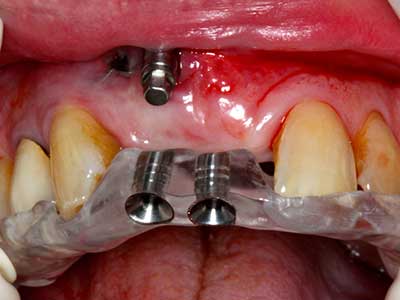

Когато се извършват хирургични процедури върху кост в непосредствена близост до чувствителни структури като кръвоносни съдове или нерви, ротиращите инструменти създават значителен риск за ятрогенно нараняване. Пиезоелектрическите апарати могат да бъдат от помощ при препарация на костно покритие и отстраняване на твърда кост близо до нерви, особено за оголване на нервите след ятрогенно нараняване, както и по време на латерализация на нервите за резекционни и реконструктивни процедури или поставяне на имплант (Фиг. 17-20). Лекият контакт между пиезонакрайника и нерва по принцип не води до нараняване, но ако действате непредпазливо с трионообразни движения или приставки за остатъчен костен субстрат, може да причините временно или перманентно увреждане на нерва. Въпреки това, рискът от увреждане се счита за много по-малък, отколкото при употреба на триони или ротиращи инструменти (Pereira, Gealh et al. 2014).